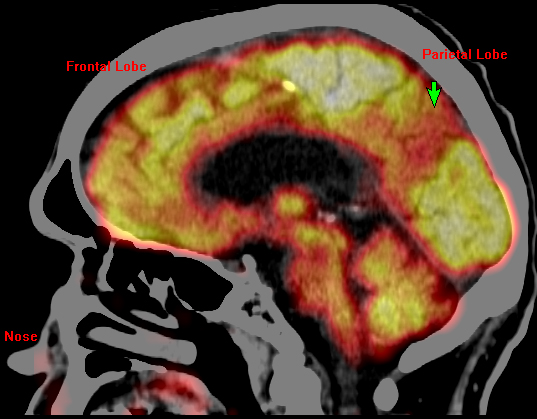

Image of glucose metabolism PET overlaid on CT in an Alzheimer's patient with mild dementia. Green arrow points to regional hypometabolism in the medial parietal lobe, (which processes biographical information and memory),a proposed biomarker for Alzheimer’s. (Credit: UB Center for Positron Emission Tomography)

Miletich said that nuclear medicine techniques exist to reveal both general regional physiology, such as glucose metabolism or blood perfusion, and specific neurochemical physiology, such as the status of the brain dopamine system. Such information is useful in the care of patients with disorders ranging from strokes to dementia.

Miletich relies on SPECT and PET/CT because these techniques reveal different patterns of physiology. These patterns are both sensitive and specific for many brain disorders.

“There are cases, such as in traumatic brain injury, where commonly used techniques, like CT and MRI show no abnormalities, but where a patient continues to be profoundly compromised in his or her daily life,” he said. “In those cases, cerebral perfusion SPECT and glucose metabolism PET/CT can reveal exactly where in the brain the injury is located and the extent of damage to the brain.

“When I image the brain with SPECT or PET/CT, I can see disorders long before they have fully developed. I can see Alzheimer’s before the patient has dementia. This will facilitate the development of abortive therapy for Alzheimer’s,” said Miletich.